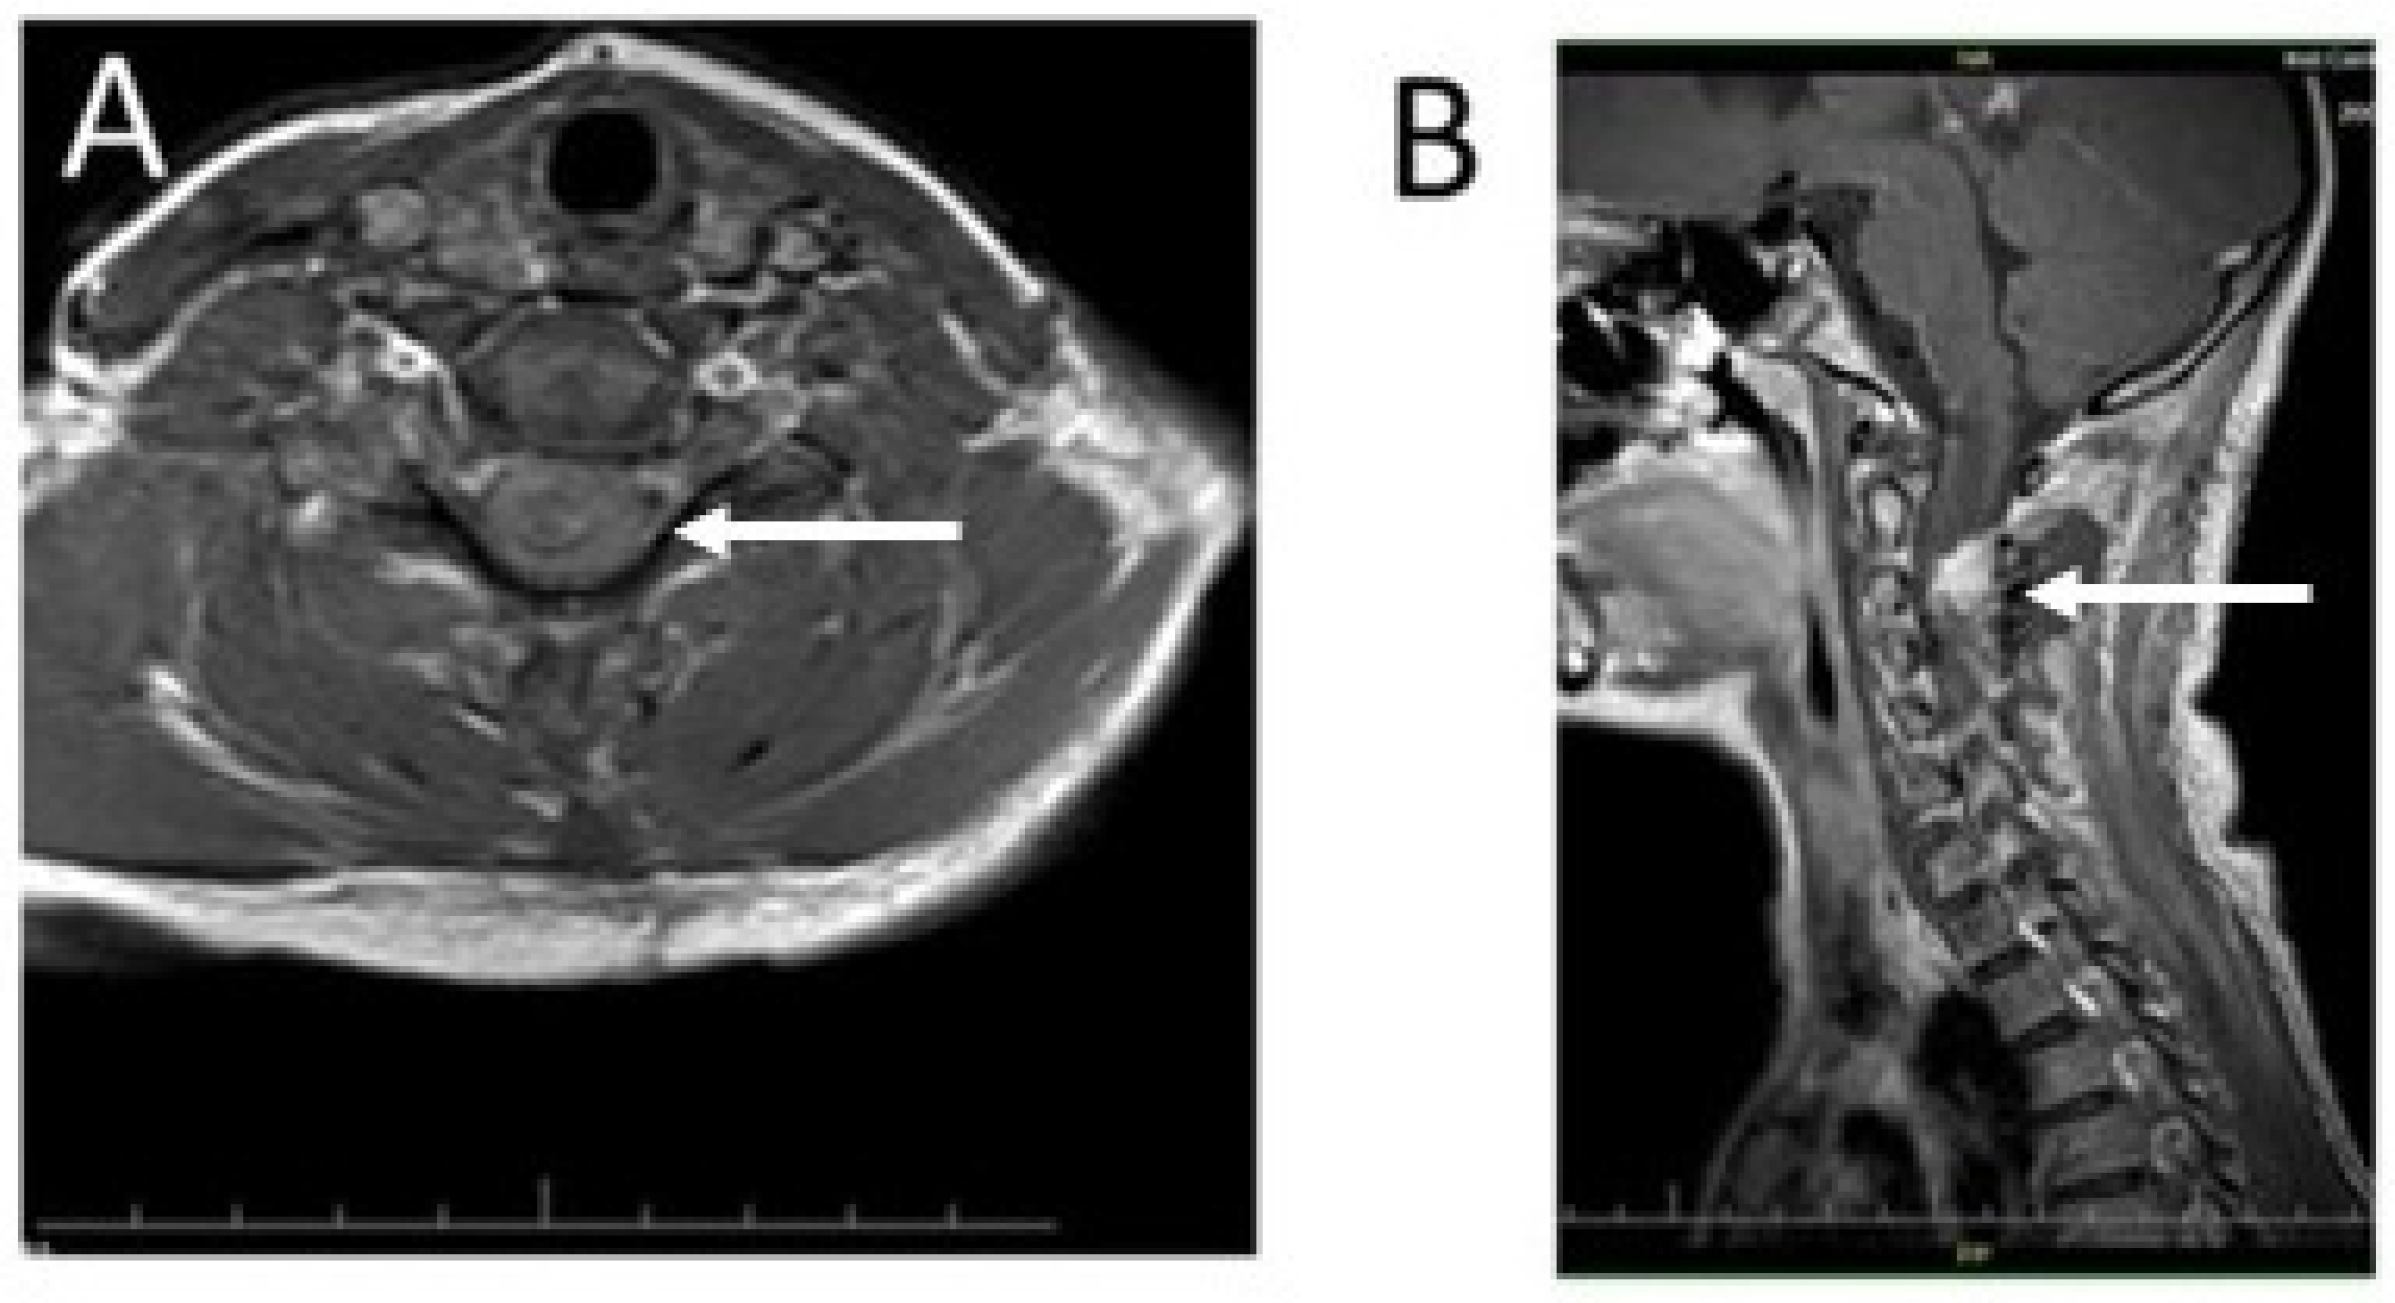

2. Case Presentation